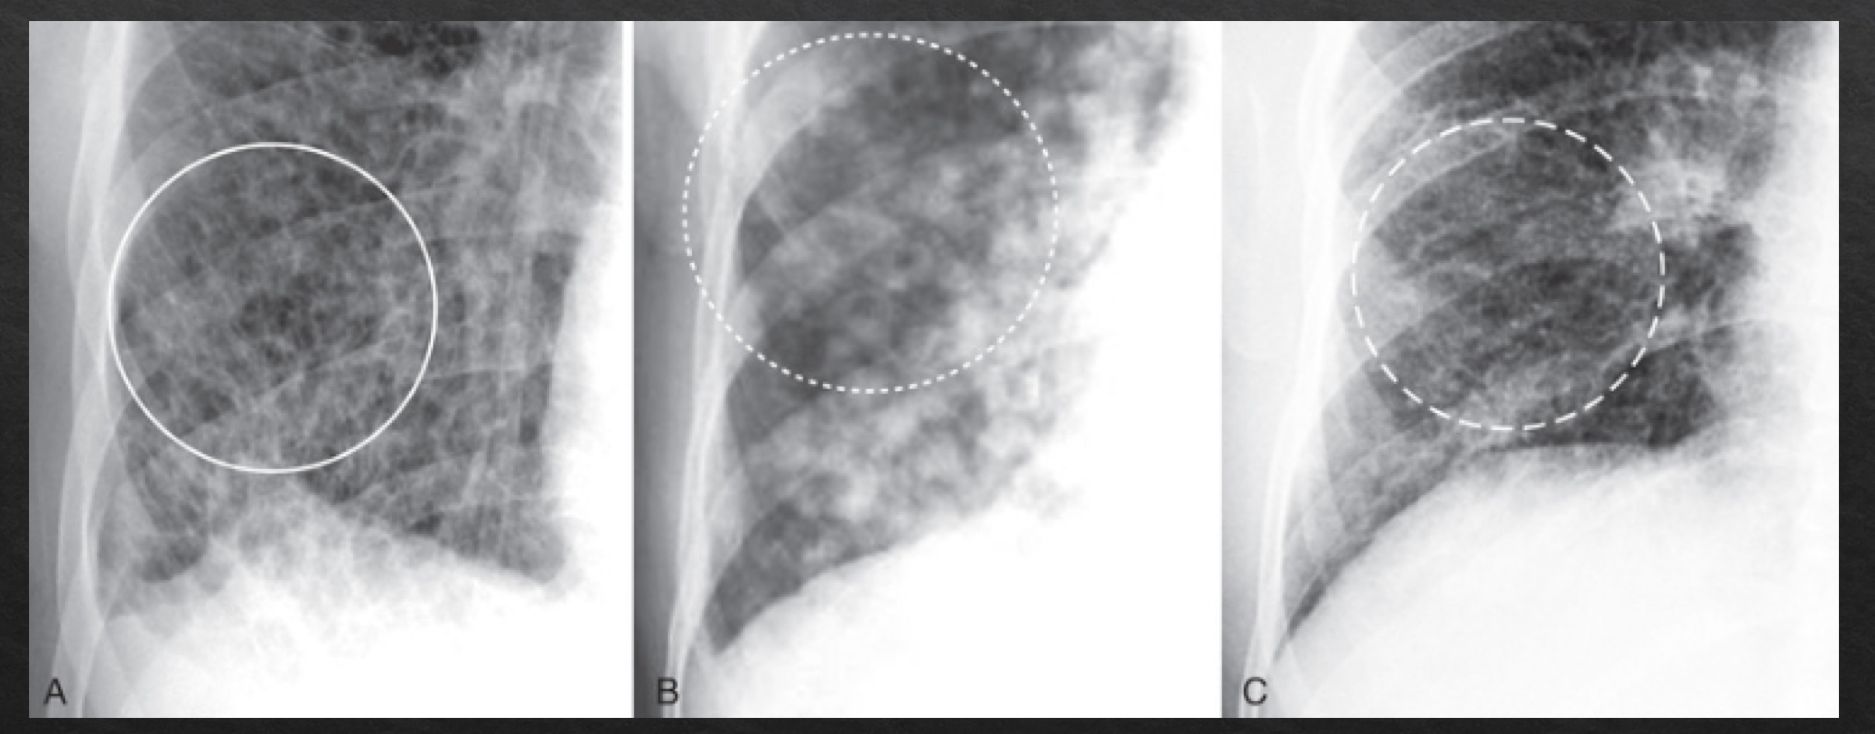

airspace disease vs interstitial disease

airspace: disease in the thin walled alveoli

fills alveolar space

interstitial (infiltrative) disease: interstitium

btwm alveoli and blood vessel

contains lymphatic vessels, fibroblasts, adn ECM proteins

thickens walls btwn air spaces

airspace disease

fluffy, cloud-like, hazy opacities

indistinct margins that blend together

may contain air bronchograms

fluid has replaced the air normally surrounding the bronchus, trapping air inside and givngit contrast to be visible

may demonstrate silhouette sign

interstitial disease

criss cross pattern

reticular- lines

nodular- dots

reticulonodular- lines and dots

margins- sharper and discrete

radiographic characteristics: pneumonia

opacities

alveoli (airspace disease)

interstitial pneumonia- walls btwn air spaces become opaque

air bronchograms may be present- air trappe din bronchi that cant escape

clearing/resolution: typically occurs in <10days

pneumoccocal pneumonia may clea within 48 hrs